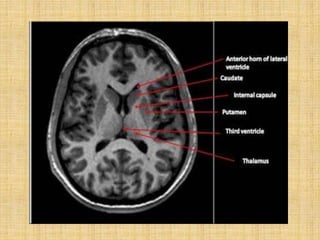

It is a C shaped mass of grey matter

Consists of large head, body and

•Head - bulges into anterior horn of

continuous with the putamen.

Caudate nucleus

nucleus inferiorly. This region is called fundus striati.